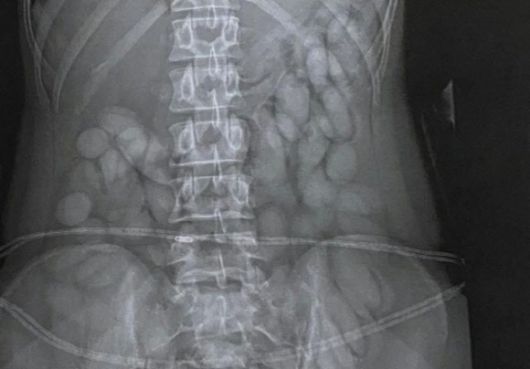

오스트리아 남성의 장 내부에서 255정의 메스암페타민(필로폰)이 발견됐다. 방콕포스트 캡처 |

의료진은 곧바로 수술에 들어갔고 세 개의 주머니에서 총 255정의 빨간 알약을 제거했다. 확인 결과 이 알약들은 메스암페타민(필로폰)으로 밝혀졌다. A씨는 의식을 잃은 상태였지만 경찰은 의료진의 협조를 통해 해당 알약들을 증거품으로 확보했다. 경찰은 “환자가 깨어나면 심문 뒤 사법처리할 방침”이라고 밝혔다.